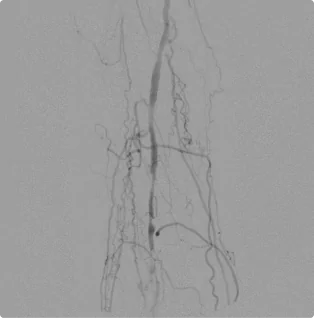

Male – Age 68

Referred by his Podiatrist for Terrible Pain In his Calf and for Arterial Evaluation

This patient saw so many specialists for his excruciating right calf pain that he lost count. After his first ultrasound at Pedes Orange County, he was diagnosed with critical arterial disease and scheduled for intervention. Only one of the three arteries in the lower leg remained open, and his calf was starving of blood flow. After three attempts at intervention, Dr. Goldstein was able to open up flow into the back of the calf and alleviate his severe pain by utilizing advanced interventional techniques to come from the bottom of the foot and work upwards. Many other vascular specialists would have considered his situation impossible and quickly referred him for invasive surgery. Closely monitoring his arterial flow for follow-up intervention has allowed him to return to a normal life.

Before

Before interventing, the artery on the front foot flows well, but the lack of flow to the back of the calf causes severe cramping and pain.

After

Intervention from the bottom opened the second branch giving blood to the calf muscle and eliminating the cramping and pain.